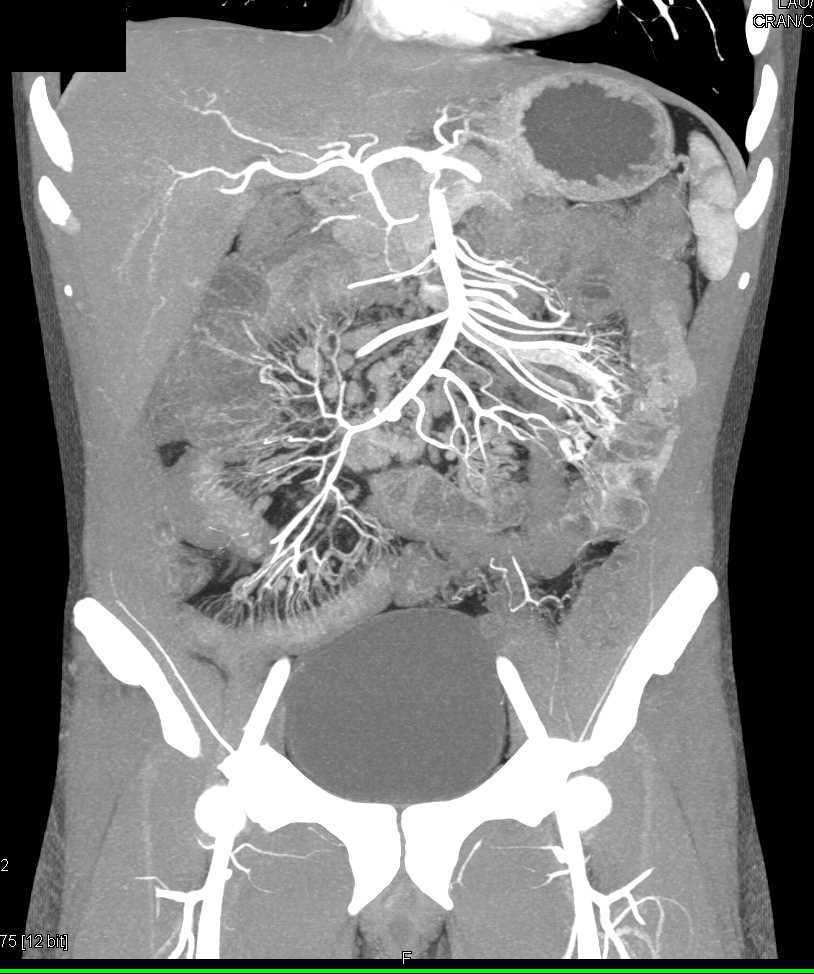

Pneumatosis Right Colon with Thrombus in Portal Vein and Superior Mesenteric Vein (SMV)